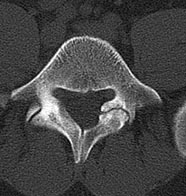

44 year old man with severe low back pain with intermittent radiation of the pain down the right leg. After undergoing conservative treatment, continued to have debilitating pain. MRI revealed a right paracentral disc herniation but CT scan revealed a unilateral pars fracture. After debating on microdiscectomy vs fusion, patient elected to undergo lumbar fusion. 4 months postop patient returned to surfing again. 9 months postop patient wrote “My recovery continues to do very well and we just got back from 8 days camping which including mountain biking, hiking, and a lot of work. Surfing almost every day and life is good…you have helped get my life and my families life back to normal.”